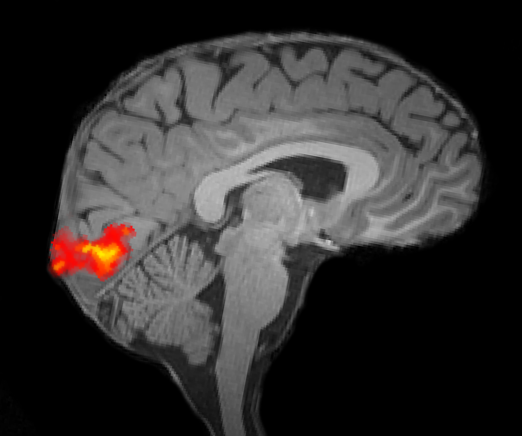

Using this novel approach, we have established that sensory uncertainty is represented in neural population activity. For example, we have found that uncertainty about the orientation of simple line elements, or the direction of movement of clouds of dots, is represented in neural activity in the human visual cortex.

localizer-activation.png